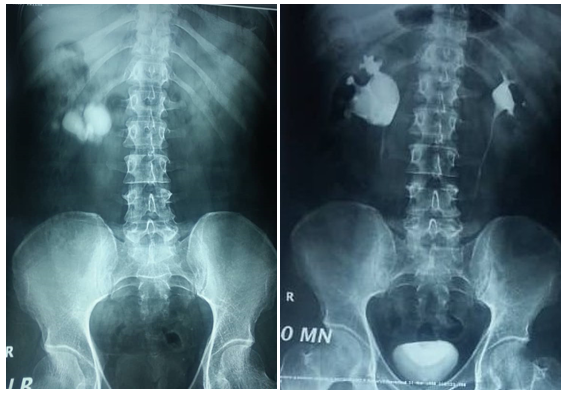

45 years old male patient came to urology outpatient complaining of recurrent right flank pain for several months, no fever or hematuria, no significant medical or surgical history. Physical examination was unremarkable, serum creatinin 1.1mg/dl , urine analysis showed microscopic hematuria, urine culture was negative, ultrasound reveals multiple right renal stones with dilated extrarenal pelvis, plain x ray & intravenous pyelography performed Figure1 (A & B). All treatment options explained to the patient and after discussion he elected to undergo laparoscopic peylolithotomy. Transperitoneal laparoscopic pyelolithotomy was performed in lateral position with Rt. Flank tilted 45 degrees using 4 ports. multiple renal pelvis and calyceal stones extracted and putted in a bag made of No 6 surgical glove (Figure 2) after closure of the pyelotomy by intracorporeal sutures the bag containing the stones extracted through the umbilical port after enlarging it (Figure 2), during extraction the bag was broken and some stones escaped to the abdomen. Another bag replaced and most of the stones extracted searching for the remaining stones in the abdomen was frustrating and we decided to terminate the procedure and closing the port sites. The post-operative course is unremarkable and patient discharged in fifth post-operative day. Follow up plain x-ray after one month revealed tow round stones with 30 and 10mm maximum diameter lying deep in the pelvis (Figure 3), after discussion with the patient about the possible complications of those stones he agree to underwent open extraction by low midline incision and stones extracted.

Figure 1 Pre operative Pain abdominal x ray (A) and intravenous pyelography (B).